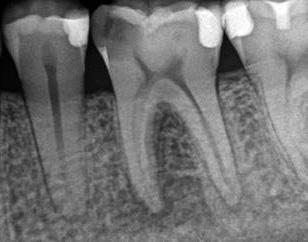

6. a–d. ábrák: A bal alsó második nagyőrlőfogon (3.7) kialakított konzervatív hozzáférési nyíláson keresztül végzett endodonciai kezelés lépései. A mezialis gyökér jelentős mértékben görbült. A gyökértömés hidraulikus kondenzációs technikával készült.

egyszerű obturációs technika, az anyag viszkozitási tulajdonságai és a pulpakamra viszonylag egyszerű tisztíthatósága a kezelésünk prognózisának veszélyeztetése nélkül teszi lehetővé az endodonciai beavatkozások lehető legkonzervatívabb módon történő kivitelezését. A bemutatott esetek ellátása során az Aurum Blue rendszert (Meta Biomed) használtuk a gyökércsatornák megmunkálására, míg a gyökértömés elkészítése során hideg hidraulikus kondenzációs technikát alkalmaztunk a kalcium-szilikát alapú CeraSeal (Meta Biomed) sealer felhasználásával (8. ábra).